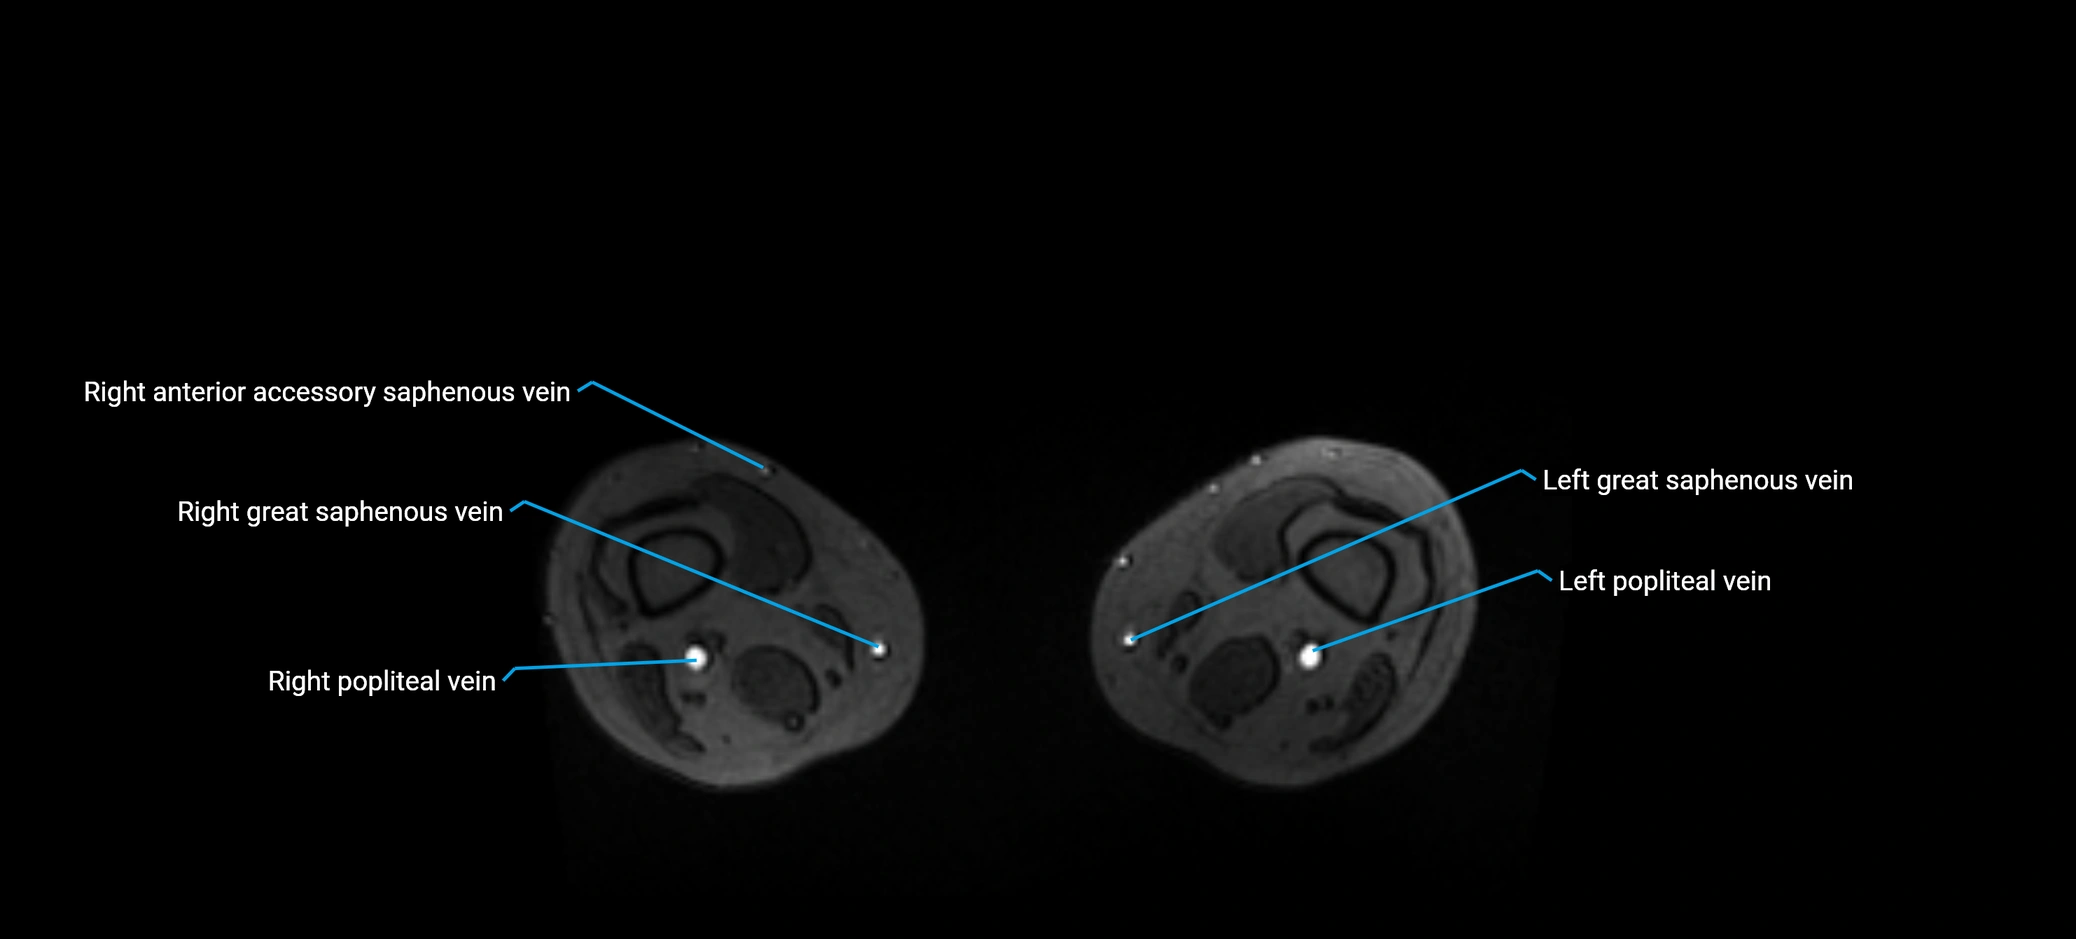

MRI image

image